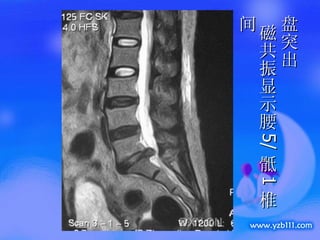

盘突出  磁共振显示腰 5/ 骶 1 椎间